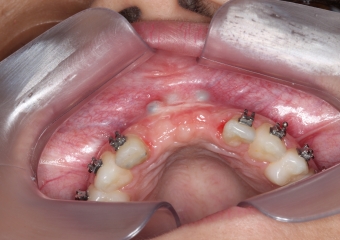

Imagem após enxerto ósseo